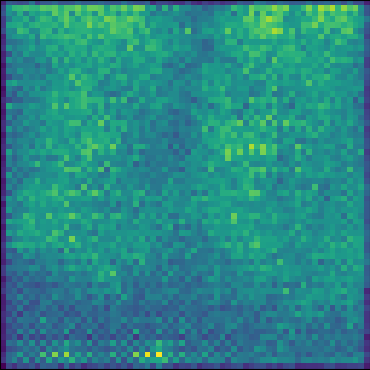

Refer to caption

(h) (d)

(i) (e)

Figure 2: Fusion process applied to an image from the tail class Tortuous Aorta (a.1) and one of its neighbor images from the head class Atelectasis (b.1). (a.2) and (b.2) are channelwise Maximum Intensity Projections of the sparse vectors obtained from (a.1) and (b.1) respectively. In (a.3) and (b.3), we use EigenCAM to find attention maps for each sparse vector and define binary masks (yellow is one and dark purple is zero) using τh=τl=0,4formulae-sequencesubscript𝜏subscript𝜏𝑙04\tau_{h}=\tau_{l}=0,4 as thresholds. We combine the masked sparse vectors into (c) and decode the vector into a fused image (d). Finally, we apply five inference steps in (e) to obtain a less noisy image.